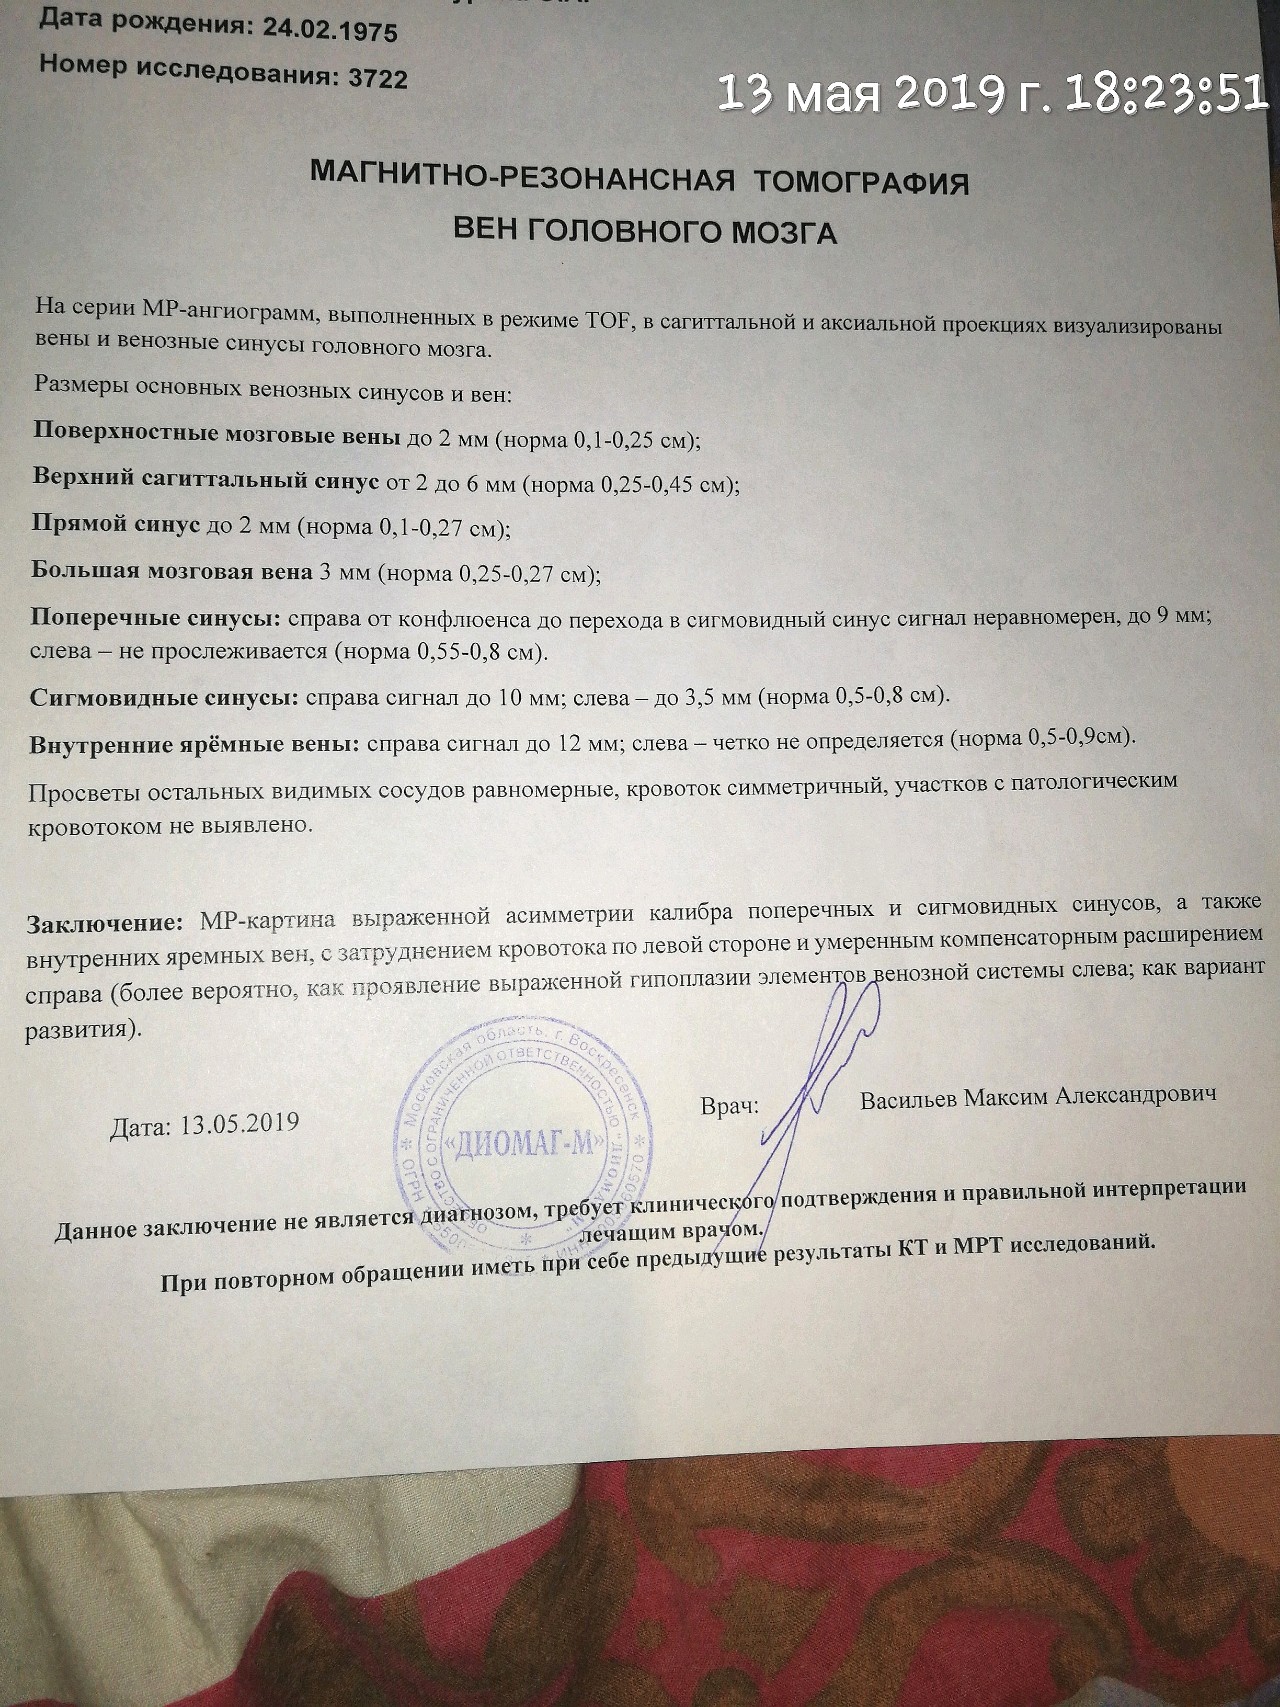

Демиелинизирующие заболевания мозга: МРТ изображения

Раздел: Путеводитель по жизни